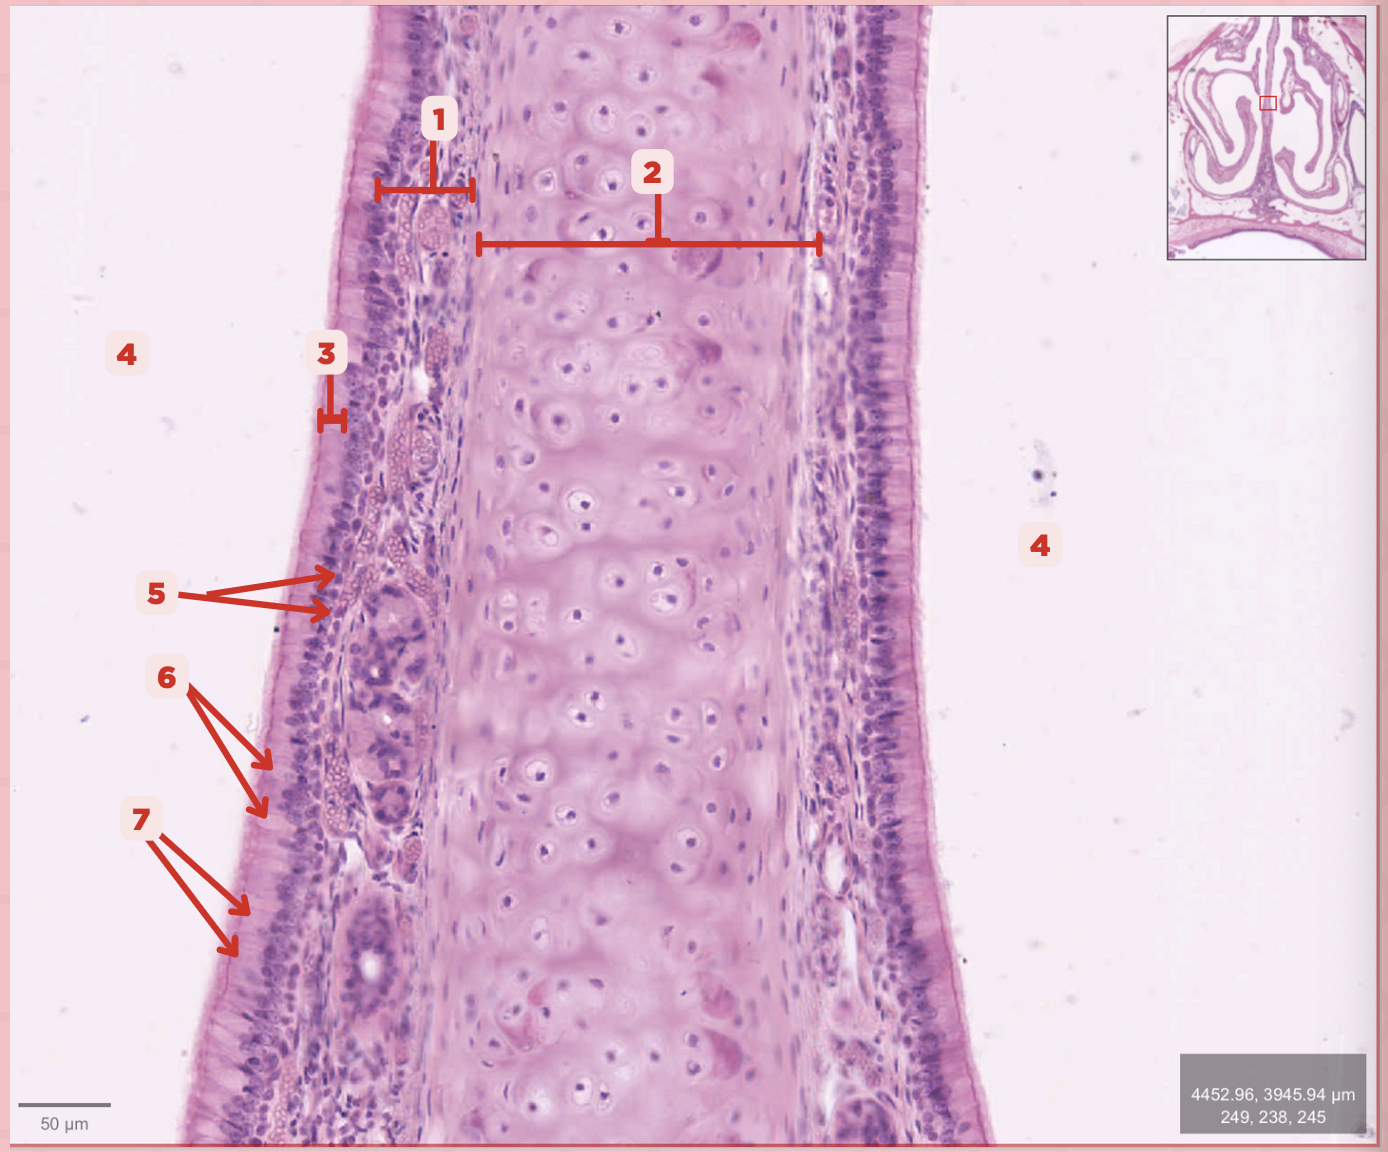

Identify the structure labeled as 1.

Hyaline Cartilage

Identify the structure labeled as 2.

Respiratory Epithelium

Identify the structure labeled as 3.

Nasal Cavity

Identify the structure labeled as 4.

Basal Cells

Identify the structure labeled as 5.

Goblet Cells

Identify the structure labeled as 6.

Ciliated Columnar Cells

Identify the structure labeled as 7.

Adipose tissue

What type of tissue is sometimes seen between the bony spicules?

Serous and Mucous Glands

What glands are present in the Lamina Propria?